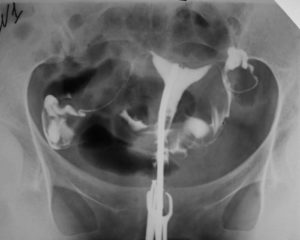

Сущность гистеросальпингографии состоит в заполнении маточной полости и ее труб особым веществом, которое называют контрастным. Вводят его с помощью катетера через влагалище.

Исследование проводят двумя способами: с помощью УЗИ и рентгена. Введенное вещество помогает выявить спайки маточных труб, воспалительные процессы, новообразования.

После обработки антисептиком с помощью катетера в полость матки направляют контрастное вещество. В тот момент, когда жидкость наполняет матку и трубы, делается ряд рентгенограмм, на которых зафиксированы результаты исследования.

Вначале жидкостью заполняют матку, делая нужное количество снимков. Затем, чтобы проверить проходимость труб, вводят дополнительное количество раствора.

Под напором краситель вытекает в трубы, а снимки фиксируют возможности их проходимости.

Результаты двух методик с достоверностью «расскажут» о состоянии матки и труб. Расшифровка снимков проста: проходимость маточных труб диагностируется в том случае, если введенное вещество, свободно циркулируя по матке и трубам, выходит в полость брюшины.

На рентгеновских снимках видно, как контрастное вещество проходит сквозь маточные трубы. Если жидкость заполнила трубы и попала в брюшную полость, врач удостоверяется в проходимости маточных труб. В том случае, если жидкость не полностью проникла в трубы и остановилась на определенном уровне, специалист подтверждает наличие непроходимости и назначает дальнейшее лечение.